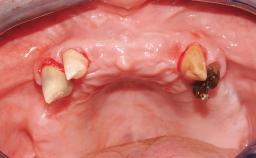

Surgical treatment of a 68-year-old female patient who experienced failure of her conventional bridge in the right maxilla. After removal of the compromised abutment teeth and a healing period of 6 weeks, a sinus floor elevation procedure using the lateral window technique and a composite graft to correct the insufficient bone height is carried out.

Two dental implants are placed in the same surgical session. The case concludes with the presentation of the final fixed dental prosthesis with a distal cantilever unit.

Bone Augmentation Simultaneous|Sinus Floor Elevation

Augmentation Materials Autogenous chips|Xenogenous